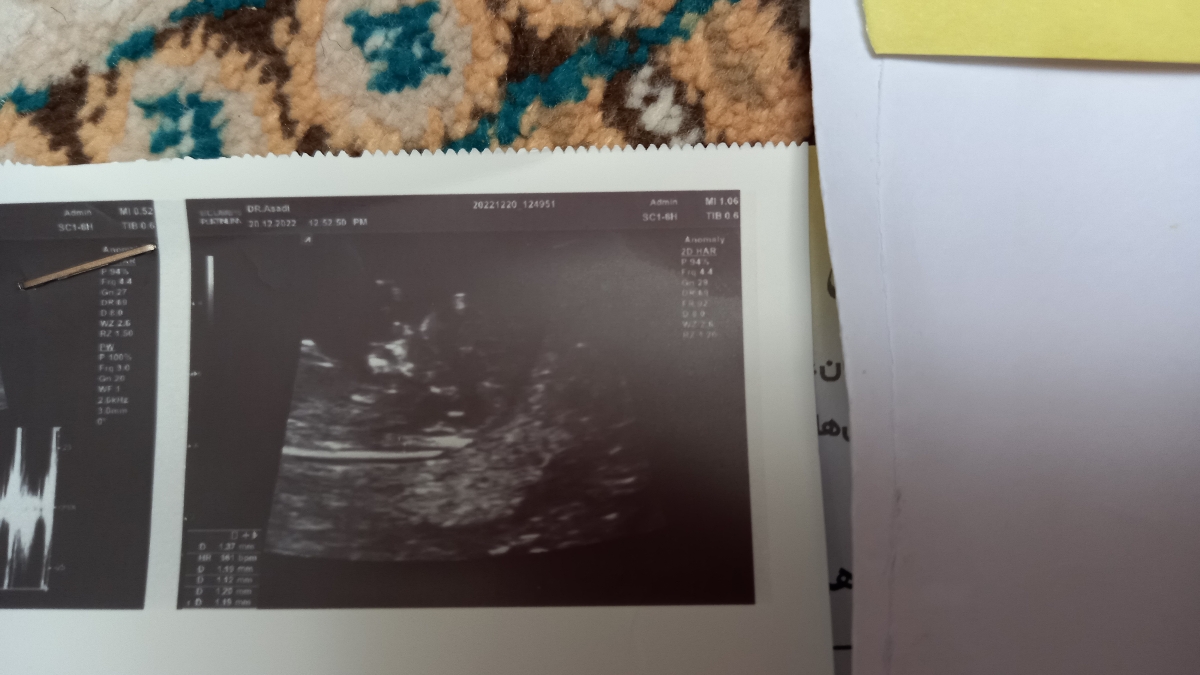

❓❓تفسیر سونو ان تی و تعیین جنسیت

همه چی خوبه

فقط جفتت پایینه باید هیلی استراحت کنی تا بره بالا و چند وقت سونو مجدد بدی وضعیتشو بررسی کنی

عزیزم واسه جفتت که پایینه استراحت داشته باش بقیه چیزا خوبه

پسره

جنسیتم فکر کنم پسره،بچه اولتون چیه؟

شبیه دختر...سونو چی گفت؟

سونو گفت ب دختر میخوره

خط اخر نوشته famale

واقعا تو سونو ذکر کرده...چه جالب تا حالا ندیده بودم تو سونوی ۱۲ هفتگی بزنه😅

تو آنومالی میزنن ولی تو nt ندیده بودم

نوشته احتمالا دختر